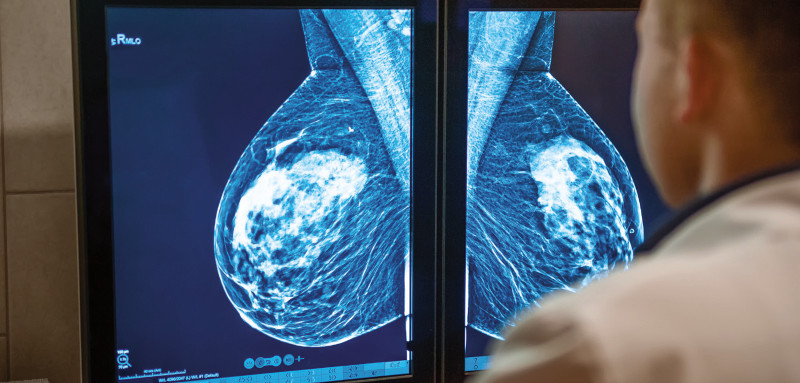

O câncer de mama é o mais comum entre as mulheres e é definido como um tumor maligno que se desenvolve nas células do tecido mamário. O primeiro sintoma dessa doença para a maioria das mulheres é o aparecimento de um nódulo duro (caroço) e de formato irregular em uma das mamas. Por isso, quanto mais cedo for detectado, por meio de um exame de “screening”, e tratado, maiores são as chances de cura completa.

Hoje em dia, as intensas campanhas para detecção precoce do câncer de mama têm tido um efeito muito grande na redução da taxa de mortalidade dessa doença. Hoje em dia, a recomendação varia um pouco de acordo com as diferentes organizações, mas é consenso que a mulher entre 20 e 39 anos deve ter a mama examinada por um profissional de saúde a cada três anos, e que após os 39 anos, deve ser anual. A mamografia ainda é a forma de melhor detecção precoce do câncer e deve ser feita a partir dos 40 anos anualmente, e mais cedo dependendo dos fatores de risco. Após os 50 anos, pode ser feita a cada dois anos, também dependendo dos fatores de risco de cada um.

Caso exista alguma imagem suspeita na mamografia, você será orientada a voltar e fazer imagens mais concentradas na área suspeita. Muitas vezes, o exame é completado com ultrassonografia. Caso esses exames confirmem que existe uma área suspeita, o próximo passo é uma biópsia. A detecção precoce do câncer de mama pode ser a diferença entre uma excelente qualidade de vida ou um tratamento extenso e longo. Hoje em dia, a biópsia é feita guiada pela mamografia (sterotatic biopsy), com anestesia local, em ambulatório pelo médico radiologista. De acordo com o resultado, se confirmado o câncer, um tratamento específico ao tipo de células cancerosas encontradas deve ser delineado. Esse tratamento inclui remoção cirúrgica do tumor (muitas vezes apenas do nódulo) tratamento complementar com quimioterapia, radioterapia e hormonioterapia, dependendo do tipo de células encontradas e se existe algum envolvimento das glândulas linfáticas da axila (gânglios).